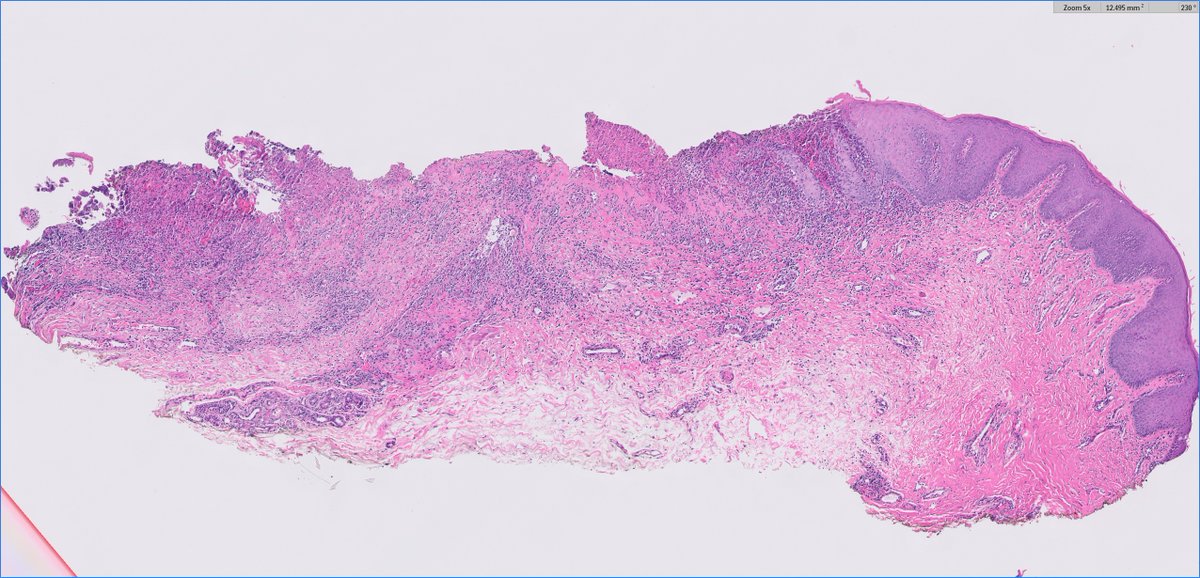

#Breastpath #Surgpath #Pathresidents #Pathtwitter Resection of a suspicious breast mass in a 60 year old woman. Take a look at some images, place your vote, and read some discussion.

BrownPathology's tweet image. #Breastpath #Surgpath #Pathresidents #Pathtwitter

Resection of a suspicious breast mass in a 60 year old woman.  Take a look at some images, place your vote, and read some discussion.